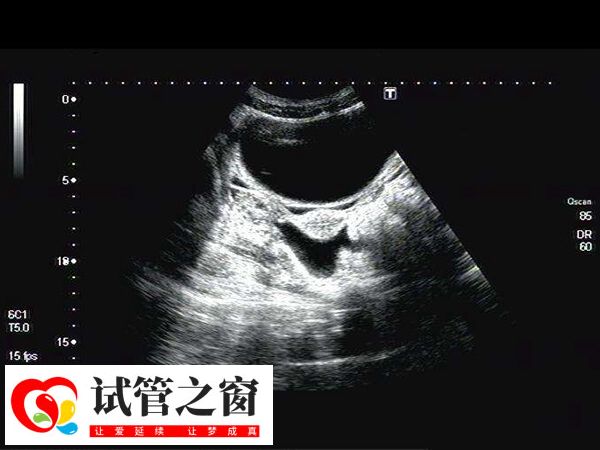

囊胚移植后1到14天變化是怎樣的

囊胚移植后1到14天的變化可以分為幾個階段,一般移植第1天到第3天,胚胎開始自由漂浮,并從卵子儲備和宮腔內液體中獲取營養,而在第4天到7天會繼續分裂,尋找并準備著床,大概在移植8-9天左右就可以著床在內膜上了,以此可開始在母體內發育,并釋放出hCG(人絨毛膜促性腺激素)。